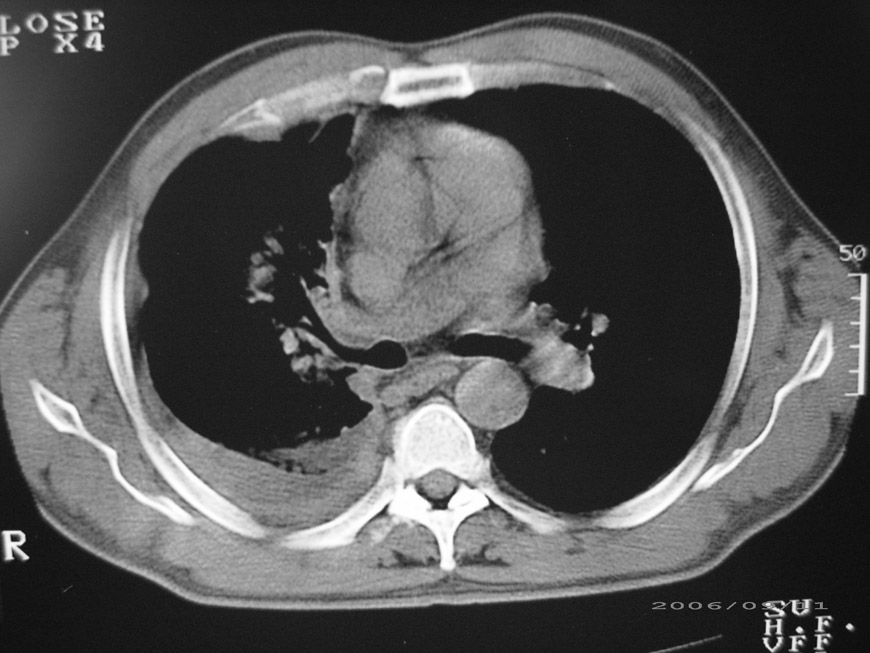

以下是引用守望可可西里在2006-9-11 15:29:00的发言:[br][br] ct平扫表现:右侧胸膜腔缩小,积液,胸膜增厚且不均匀、不规则,以纵隔胸膜增厚为主,边缘呈锯齿状,并见附壁内突之结节状肿块影。右肺含气量减少,纹理聚集,右肺门中下部见数个肿大的淋巴结。纵隔无移位,内未见明显肿大淋巴结,双侧主支气管以及各叶、段支气管比较通畅。。[br] 考虑:右侧胸膜恶性间皮瘤,伴肺门淋巴结转移。